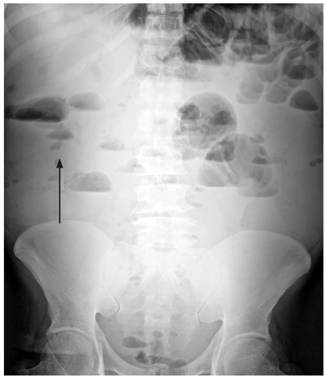

Se inició el manejo con líquidos intravenosos (y se logró normalidad hemodinámica) y cubrimiento antibiótico a base de ampicilina/sulbactam. Se solicitaron estudios paraclínicos que mostraron un hemograma con leucocitos: 15 530/μL, hemoglobina: 10,4 g/dL y plaquetas: 130 000/μL, además de proteína C-reactiva (PCR): 114 mg/dL, gases arteriales con pH: 7,31, presión parcial de dióxido de carbono (pCO2): 22,7 mm Hg, presión parcial de oxígeno (PO2): 70,3 mm Hg, bicarbonato (HCO3): 11,2 mmol/L y base exceso (BE): -12,7 mmol/L. Se realizaron radiografías de tórax de pie (Figura 1) y de abdomen simple (Figura 2).

Se presenta el caso de un adulto mayor, quien consultó por dolor abdominal agudo de características descritas, asociado con manifestaciones psiquiátricas compatibles con delirio. Clínicamente se encontraron datos de síndrome de respuesta inflamatoria sistémica (SIRS) con un qSOFA positivo >2 10. Se tomaron estudios paraclínicos que reportaron reactantes inflamatorios altos y hemograma con desviación a la izquierda en el paciente con acidosis metabólica, lo que apoyó el diagnóstico de sepsis 10 y ameritó una intervención guiada por metas. Durante la observación se evidenció por imágenes la ruptura de una víscera hueca y signos de obstrucción intestinal parcial 12. Por la localización anatómica del dolor se sospechó patología apendicular; sin embargo, no se descartó la posibilidad de perforación espontánea del intestino delgado. Las causas de perforación espontánea del intestino delgado aparecen en la Tabla 1.